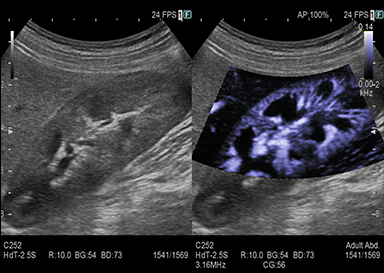

頸部(動静脈・甲状腺)、心臓、腹部(肝臓・胆のう・膵臓・脾臓・腎臓・膀胱・腹部大動脈等)、下肢(動脈・静脈)等が観察できる検査です。

超音波機器について

超音波検査では機械の性能が画質を決定します。性能の良い超音波機器での検査ではより詳細な情報が得られます。